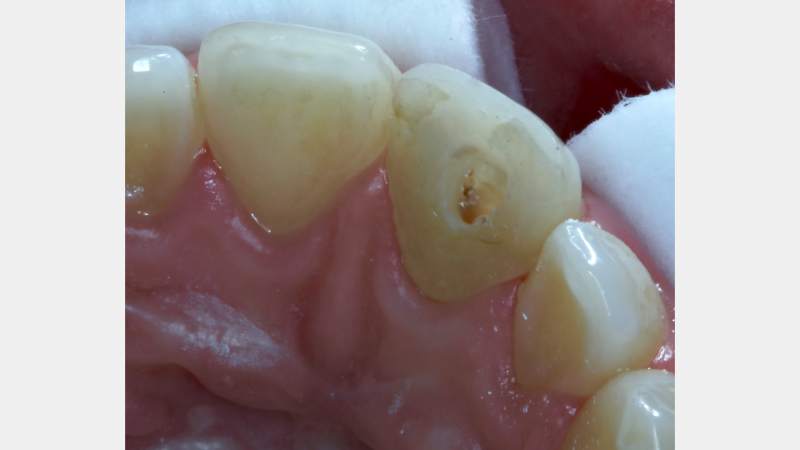

Historically, discolored anterior teeth were treated with indirect ceramic restorations, such as crowns or veneers. This can be illustrated in the case shown in Figure 1, where the discolored left central incisor (2.1), along with two other incisors, was treated with lithium disilicate ceramic veneers (Fig. 2). More recently, direct composite materials that incorporate specialized “opaquers” have also been utilized for treatment.

These strategies offer esthetic and predictable outcomes. However, this is often at the expense of tooth structure. Iatrogenic loss of tooth structure can result in premature extraction due to catastrophic fracture. This is of particular concern with non-vital teeth, which are already structurally compromised by endodontic procedures.